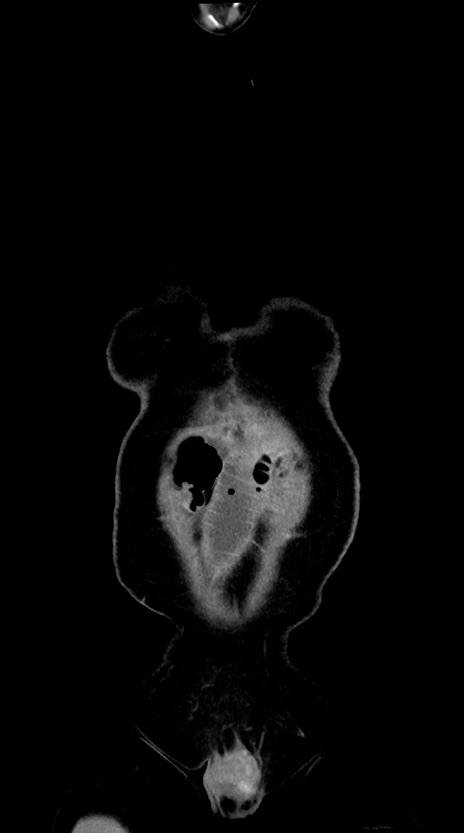

症例28(冠状断像)

【症例】60歳代男性

【主訴】嘔吐

【現病歴】胃癌にて胃全摘後。食思不振が悪化し、夜中に嘔吐することがある。

【既往歴】胃癌、胃全摘、脾摘、胆摘後

【データ】WBC 5900、CRP 10.56